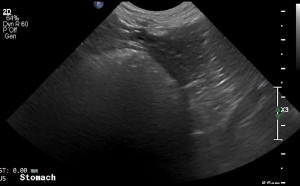

SIMON Ultrasound Database

This ultrasound database is a free resource for students and doctors!

Our collection includes videos of dogs, cats, horses, cows, humans, and many other species!